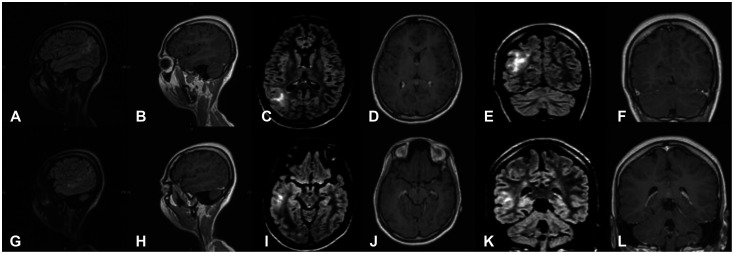

Epilepsy surgery is a well-established treatment for drug-resistant epilepsy, with awake craniotomy being used in certain cases to remove epileptogenic foci while preserving crucial brain functions. We are presenting the first reported case from Pakistan of a 19-year-old woman who underwent awake epilepsy surgery to treat cortical dysplasia. She had a history of generalized tonic-clonic seizures since her childhood and was referred to our clinic due to an increase in seizure frequency. EEG and MRI identified the epileptogenic focus in the right parieto-temporal region. The patient underwent a neuro-navigation guided awake craniotomy and an excision of the epileptogenic focus in the right parieto-temporal region. The procedure was carried out using a scalp block and dexmedetomidine for conscious sedation, enabling the patient to remain awake throughout the surgery. Intraoperative mapping and electrocorticography were used for complex multidisciplinary care. Post-resection corticography showed no spikes along the resected margins. The patient was discharged without any complications and remained free of symptoms a year after the surgery. Awake epilepsy surgery is a viable option for removing epileptogenic foci while preserving vital cognitive functions. However, it is seldom used in low- and middle-income countries such as Pakistan. The successful outcome of this case underscores the need for greater awareness and availability of epilepsy surgery in resource-limited settings. Cost-effective measures, such as using small subdural strips for intraoperative localization, can be implemented.